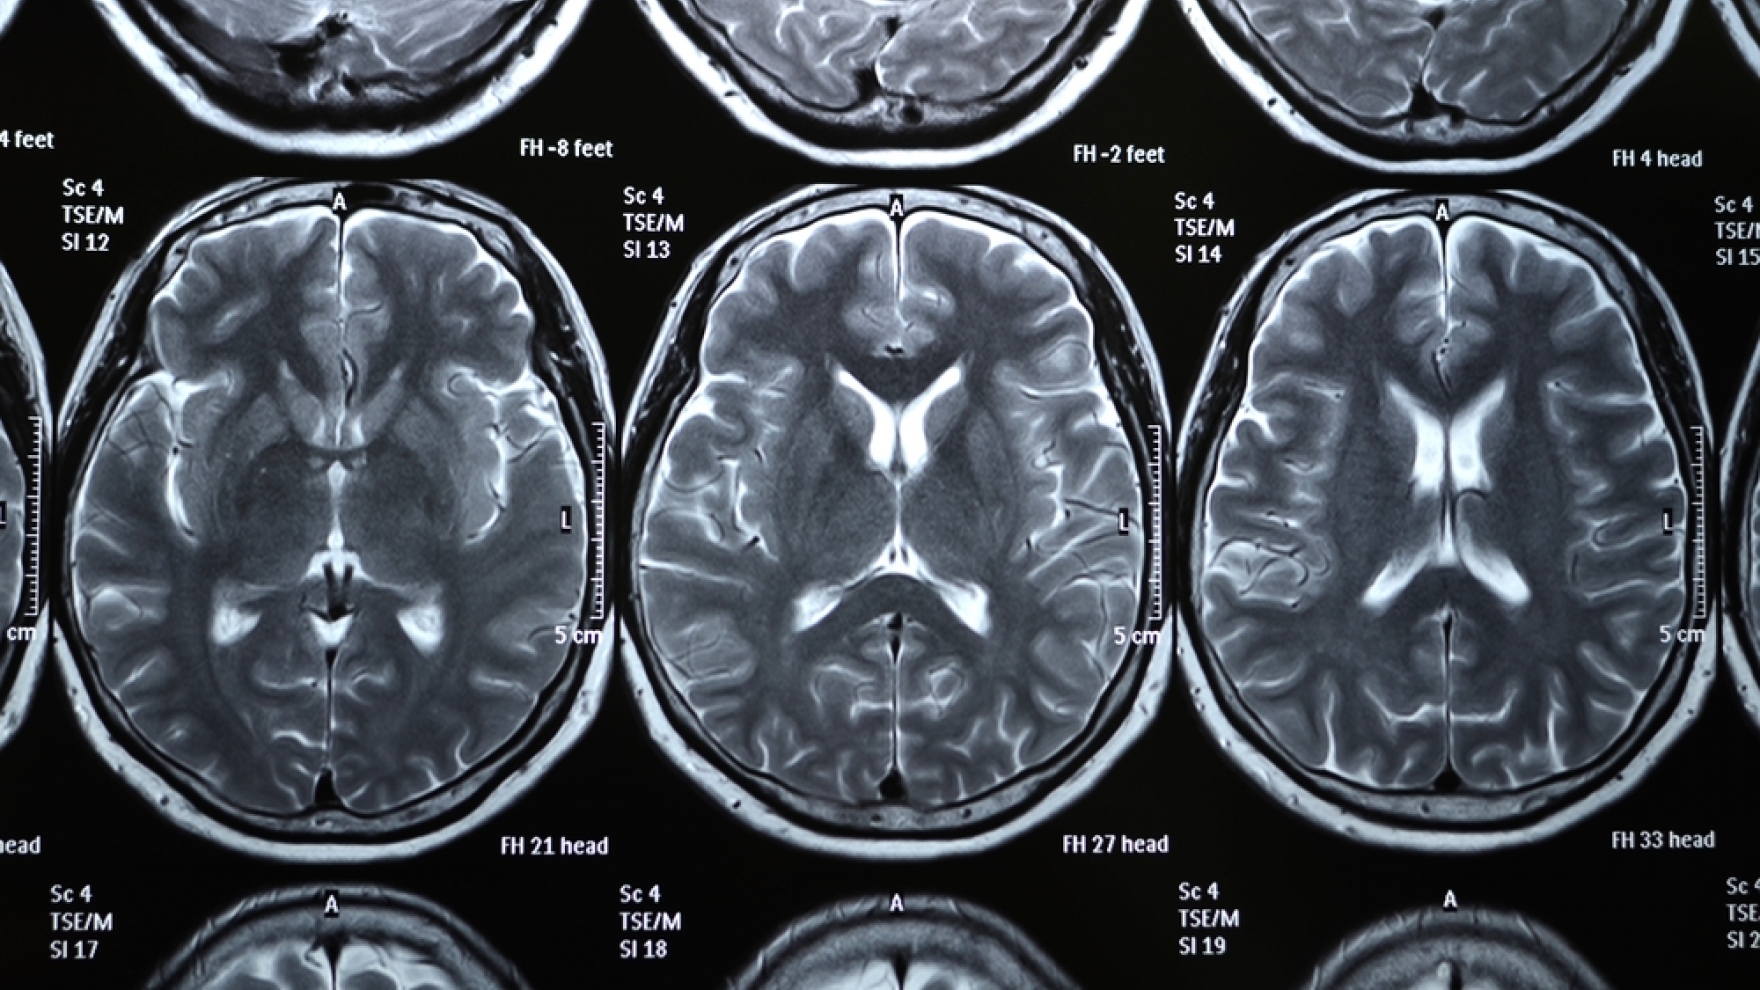

Brain x rays Free Photo Download FreeImages 2

CT Scans When Do You Need Contrast ThriveAP 3

The X ray of the Human Brain Stock Image Image of xray healthcare 8

The X ray of the Human Brain Stock Photo Image of healthcare cancer 10

14 Cool and Astonishing X Ray Images Explained 12